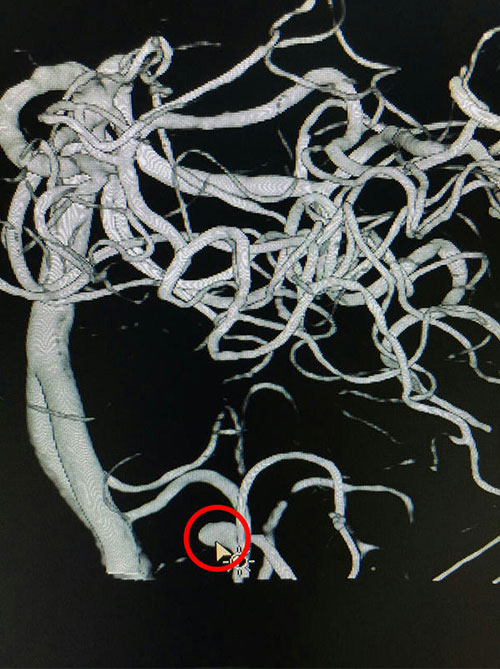

术前血管造影,红圈内箭头指向处动脉瘤瘤体

为求进一步治疗,11月22日许先生来到我院就诊,患者诉左侧肢体乏力、麻木伴吐词不清。我院神外科专家潘仁龙主任仔细诊查经后,认为患者先前脑出血诊断不明确,考虑颅脑内可能有其他问题,遂建议行全脑血管造影术检查及完善其他相关检查。11月24日DSA造影结果提示:“左小脑后下动脉瘤”,初步诊断为:1.脑干出血后遗症期;2.高血压病III级,极高危组;3.右侧面神经瘫痪。补充诊断:左小脑后下动脉动脉瘤”。